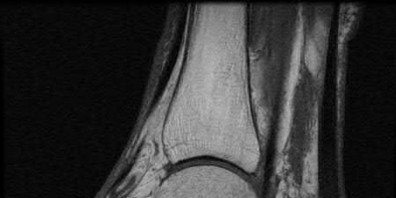

Question 8:

A 40-year-old male sustains a high-energy Pilon fracture. Initial treatment consists of a spanning external fixator across the ankle joint. Which of the following clinical findings best indicates that the soft tissue envelope has recovered sufficiently to permit definitive open reduction and internal fixation (ORIF)?

Correct Answer: Return of the 'wrinkle sign' on the anterior ankle skin

Explanation:

In the staged management of high-energy Pilon fractures, definitive ORIF must be delayed until the soft tissue envelope has adequately healed to minimize the risk of wound complications and infection. The return of skin wrinkles (the 'wrinkle sign') indicates a significant reduction in interstitial edema and is the widely accepted clinical milestone for proceeding with definitive fixation, typically 10 to 21 days post-injury.